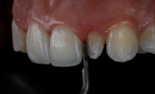

Preparo com CVDentus: Sem danos à membrana pulpo-dentinária. Preservação dos odontoblastos (CO), dentida tubular (DT), pré-dentina (PD) e zona acelular (ZA).